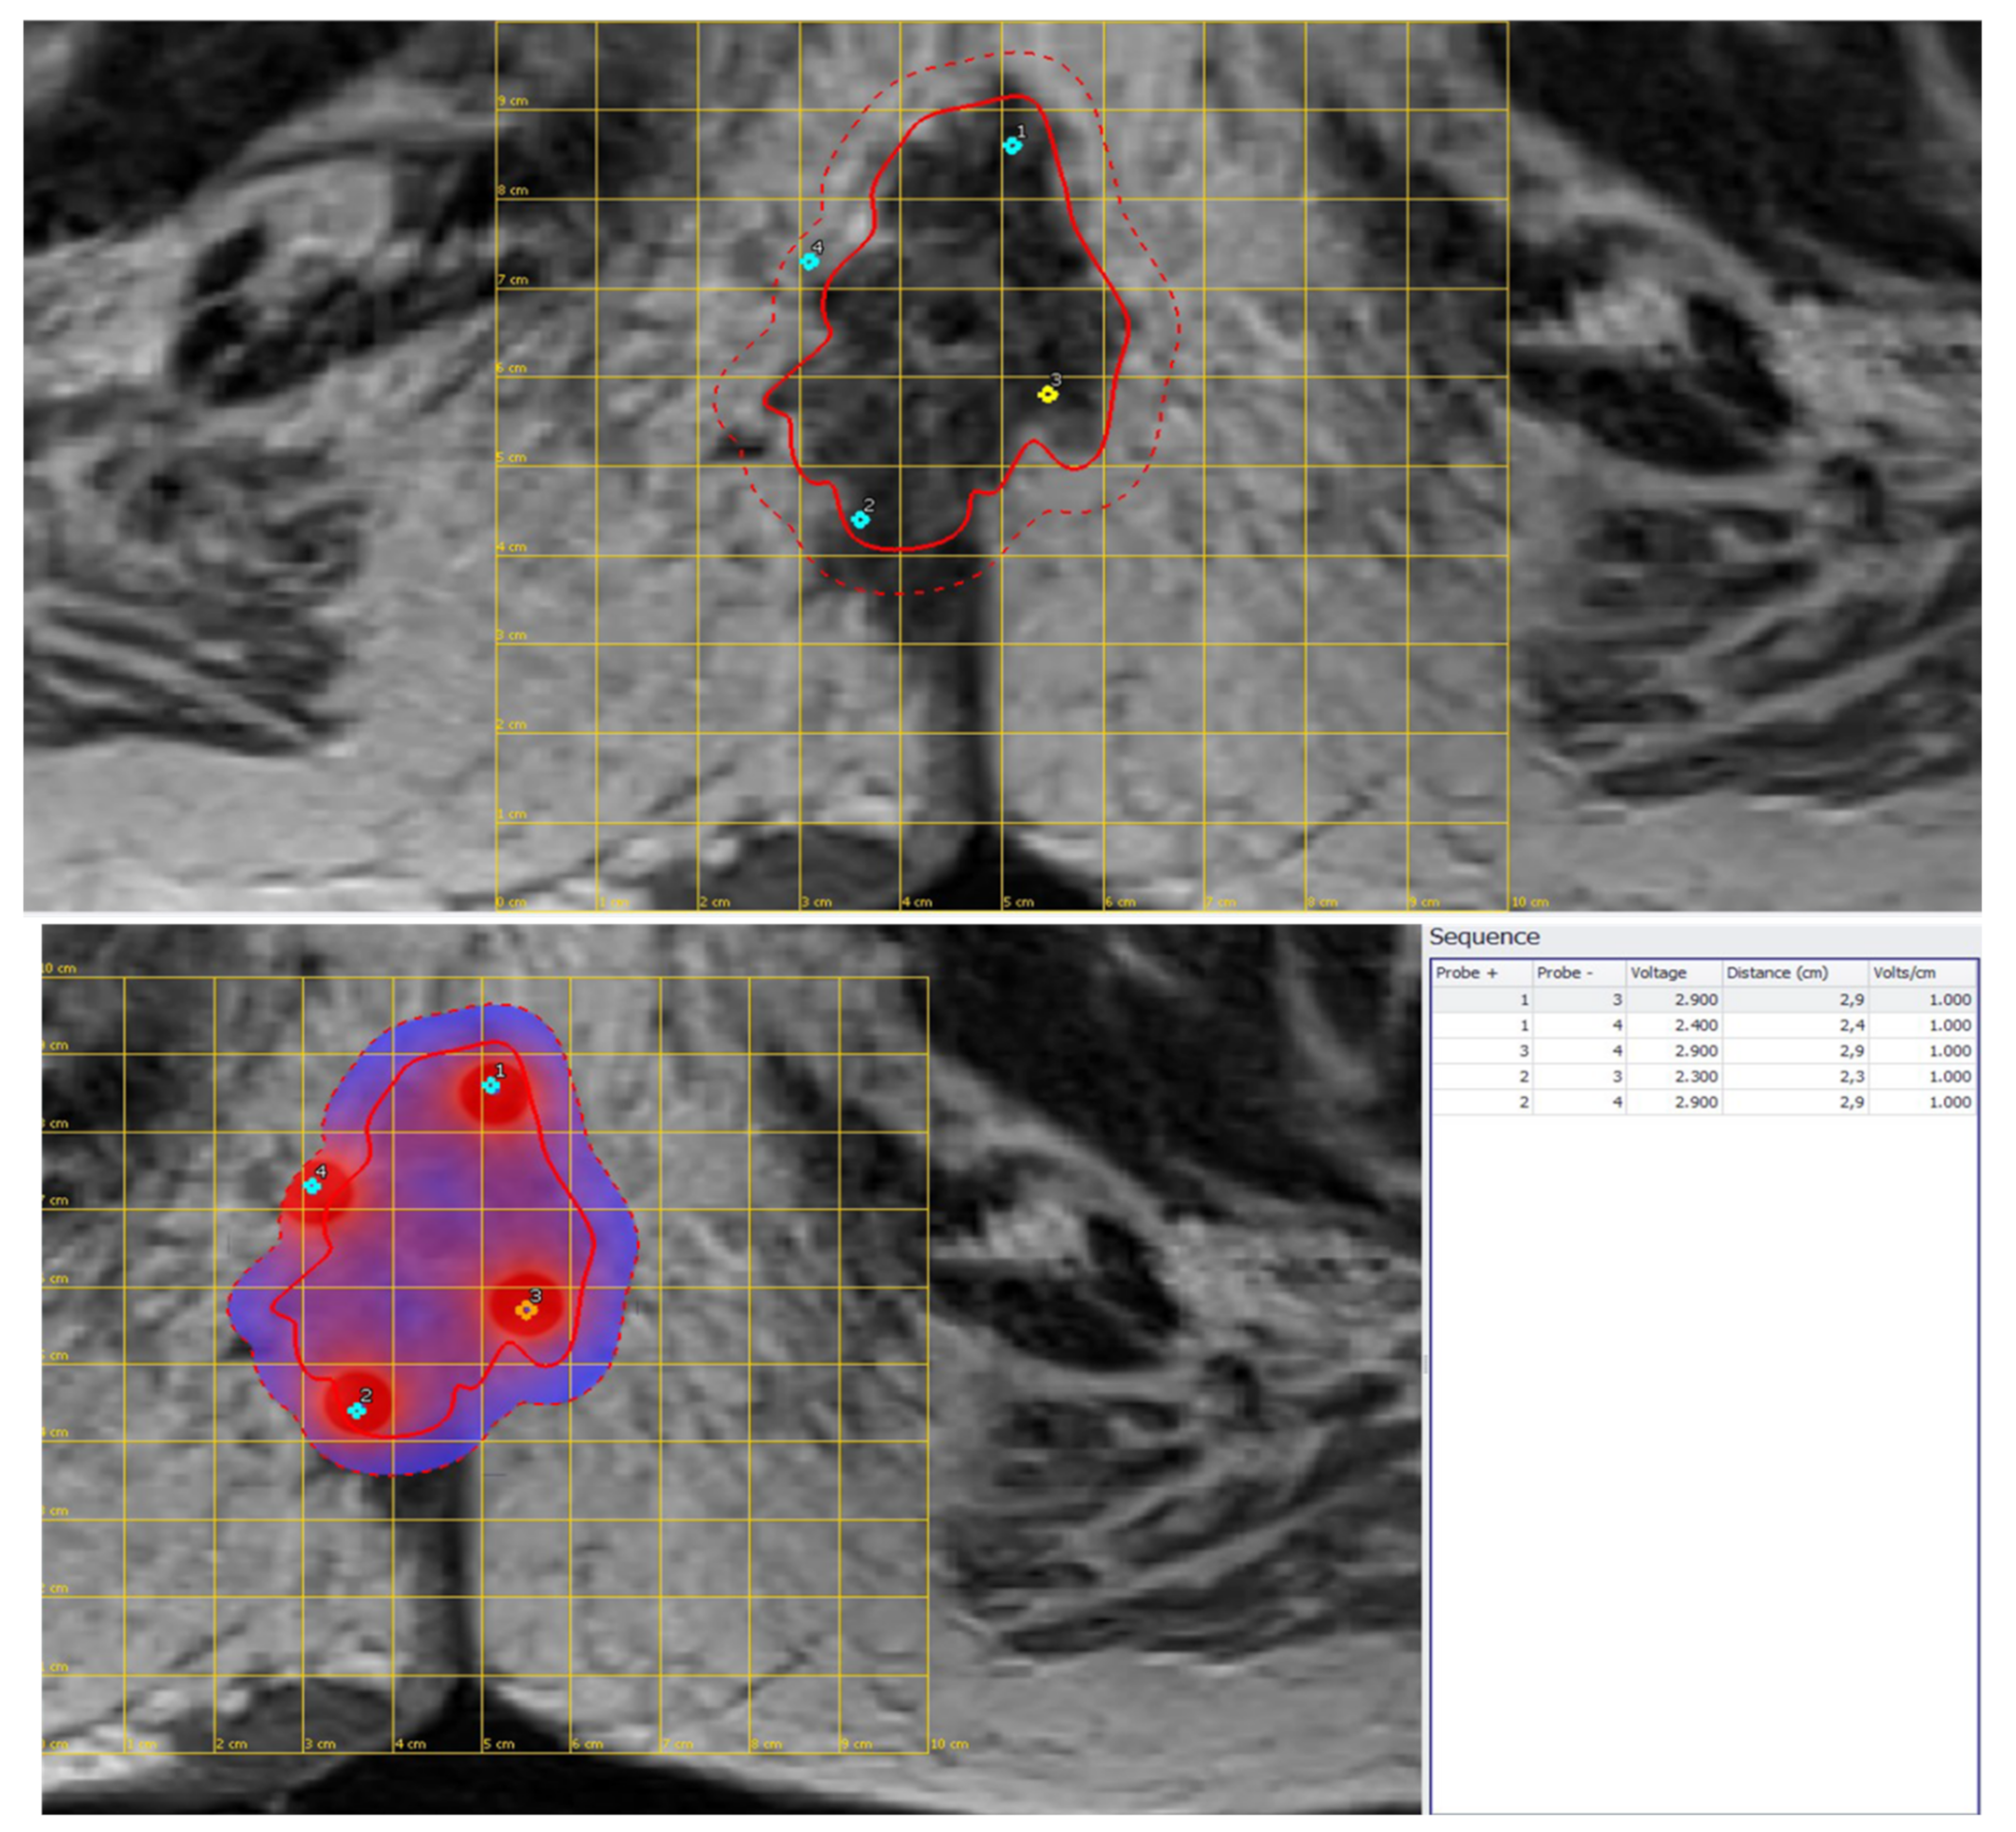

| 3 | Male 50 years old with recurrence after long course neoadjuvant therapy and total mesorectal excision (TME) treated with ECT | Variable and fixed geometry electrodes | MRI 6 months after ECT treatment showed no significant morphostructural changes in the lesion that was considered to be stable disease. Patient reported a reduction in pain on the VAS 7 to 4 scale and a reduction in bleeding. |